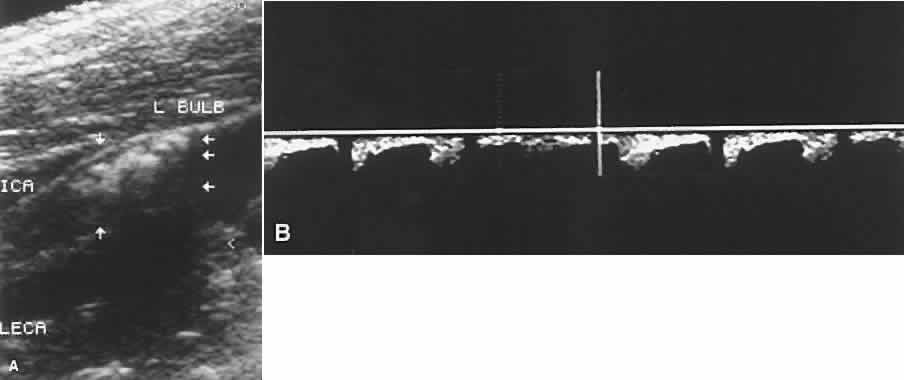

Ho and coworkers20 describe the use of CDI in the ocular ischemic syndrome. This series examines 16 eyes with ocular ischemic syndrome and shows reduced peak systolic velocities as well as increased vascular resistance in the central retinal artery and posterior ciliary arteries. Twelve of 16 eyes had reversal of ophthalmic artery blood flow (Fig. 6). This finding was thought to be quite specific for ocular ischemic syndrome by the authors, who had seen this phenomenon in multiple cases of ocular ischemic syndrome with associated internal carotid artery stenosis and only in one case of giant cell arteritis and once in an ophthalmic artery occlusion as a late development. It also was observed that the eyes in the study population with the worst visual acuity had no detectable posterior ciliary artery blood flow.

Fig. 6. A. Ultrasound of carotid artery near carotid bulb showing complete occlusion of blood flow into the internal carotid artery caused by a large plaque. B. Color Doppler image of the ipsilateral eye of the same patient showing reversal of blood flow in the ophthalmic artery as a result of the carotid occlusion.